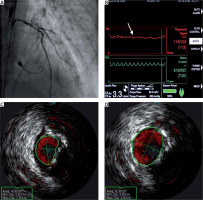

A 58-year-old man, with a history of myocardial infarction, hypercholesterolemia, smoking, arterial hypertension, chronic obstructive pulmonary disease, paroxysmal atrial fibrillation, and stroke, was transferred from another hospital to our department to undergo high-risk percutaneous coronary intervention (PCI). Previously performed coronary angiography revealed a multi-vessel disease with significant stenosis of the left main (LM) and left ascending coronary artery (LAD), as well as occlusions of the right coronary artery and circumflex artery (Figure 1 A). Due to severely depressed left ventricular (LV) function (ejection fraction of 25%) and the need for complex PCI of the last remaining vessel, after the discussion with the heart team, he was scheduled for PCI with the support of a percutaneous left ventricular assist device (pLVAD) – so-called ‘protected PCI’ [1].

A – Baseline coronary angiography of the left coronary artery: heavy calcifications, occlusion of the circumflex artery and significant stenosis in the distal part of the left main artery (LM) and proximal segment of the left descending artery, B – blood pressure curve straightening after balloon inflation in the LM (arrow), C – significant stenosis of the LM imaged in intravascular coronary ultrasound (ICUS), D – ICUS confirming an optimal stent apposition

After the initial peripheral angiography confirming eligibility for using pLVAD, a 14 Fr sheath was inserted into the right femoral artery. The Impella CP system (Abiomed Inc., Danvers MA, USA) was delivered to the LV and started providing a cardiac output of 3.4 l/min. Subsequently, intravascular ultrasound (IVUS) guided PCI using the right transradial approach was started. During each balloon inflation, the curve of blood pressure measured in the ascending aorta was flattened (Figure 1 B), which meant that cardiac output was provided only by pLVAD. Eventually, a 3.5 × 48 mm drug-eluting stent was successfully implanted in the LM/LAD (Figures 1 C, D). The femoral artery was closed with the Perclose ProGlide closure system (Abbott Cardiovascular, Santa Clara, CA, USA). Further hospitalization was uncomplicated, and after 3 days, the patient was discharged home.